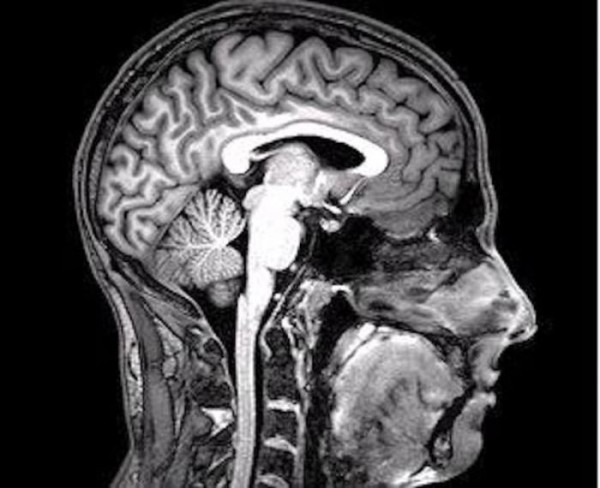

Когда мы говорим о рациональном страхе, мы подразумеваем встречу с чем-то реальным. А вот боязнь попасть в плен к космическим пришельцам может быть отнесена к иррациональному проявлению этого явления. Однако за формирование неправдоподобных страхов и неврозов отвечает конкретная зона головного мозга. Если это психологическое состояние угнетает вас, не стесняйтесь обратиться за помощью к профессионалам.